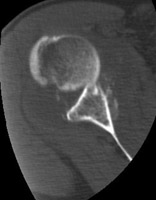

DGlenoid Fracture |

Glenoid fractures are usually the result of blunt trauma to the upper extremity. Subtle fractures can be difficult to detect on conventional radiographs; CT may be required for full diagnosis. A special glenoid fracture is termed the Bankart fracture. This consists of fracture of the inferior lip of the glenoid during anterior shoulder dislocation.